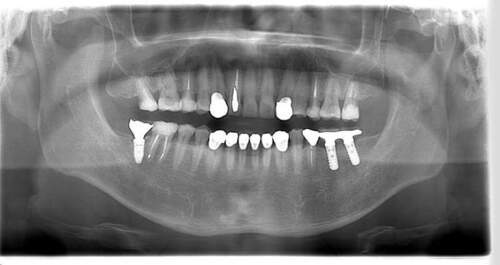

レントゲン写真

- Befor

- After

| 年齢 | 50代・男性 |

| 主訴 | 左上7番 左下5番7番 |

| 治療内容 | ・インプラント埋入 ※1:GBR(骨造成)・・・骨再生誘導法。骨の高さや厚みを人工骨や人工膜などを使用し再生する方法 |

| 治療費 | 合計:1,809,500円(税込) ■内訳 ・左上7番 ・左下5番7番 |

| 治療期間 | 左上7番約1年 左下5番7番約10ヵ月 |

| 治療方針 | 左上7番は昔他院で被せものをしており、被せものの中が歯ぐきの中まで虫歯になっていたため抜歯せざるを得ない状態だった。抜歯と同時に骨造成を行い、骨が出来るまで4ヵ月待ってからインプラントを埋入した。 ※2ポンティック・・・歯のない部分を補うダミーの歯。 |

| 担当者所見 | 元々金属の被せものが多く入っていたため、2次カリエス※3が多かった。今回は金属ではなく、ジルコニアを使用し、2次カリエスにならないよう、患者様にはブラッシング指導とメンテナンスの重要性をお伝えした。 ※3二次カリエス・・・詰め物や被せものを入れた歯が虫歯になること。 |